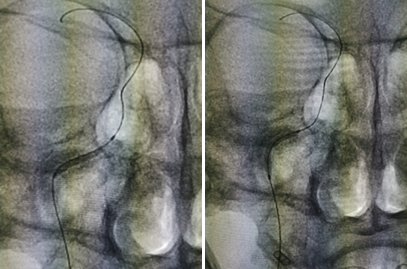

图2 造影见右侧颈内动脉起始处闭塞,闭塞处圆钝,可见自发再通后纤细扭曲血流,返流血较长,可达岩骨段-海绵窦段移行处

图3 通过前交通及后循环软膜支代偿,后交通未见明确开放,代偿情况可